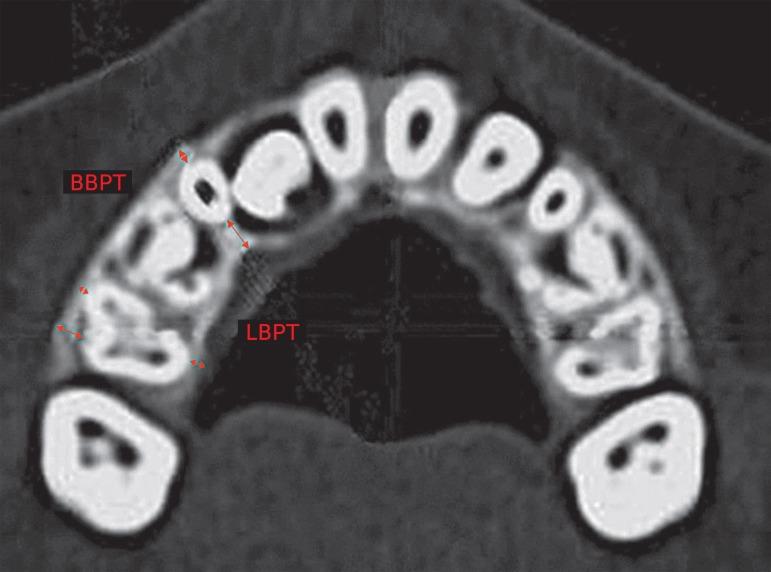

This study aimed at evaluating buccal and lingual bone plate changes caused by rapid maxillary expansion (RME) in the mixed dentition by means of computed tomography (CT).

The sample comprised spiral CT exams taken from 22 mixed dentition patients from 6 to 9 years of age (mean age of 8.1 years) presenting constricted maxillary arch treated with Haas-type expanders. Patients were submitted to spiral CT scan before expansion and after the screw activation period with a 30-day interval between T1 and T2. Multiplanar reconstruction was used to measure buccal and lingual bone plate thickness and buccal bone crest level of maxillary posterior deciduous and permanent teeth. Changes induced by expansion were evaluated using paired t test (p < 0.05).

Thickness of buccal and lingual bone plates of posterior teeth remained unchanged during the expansion period, except for deciduous second molars, which showed a slight reduction in bone thickness at the distal region of its buccal aspect. Buccal bone dehiscences were not observed in the supporting teeth after expansion.